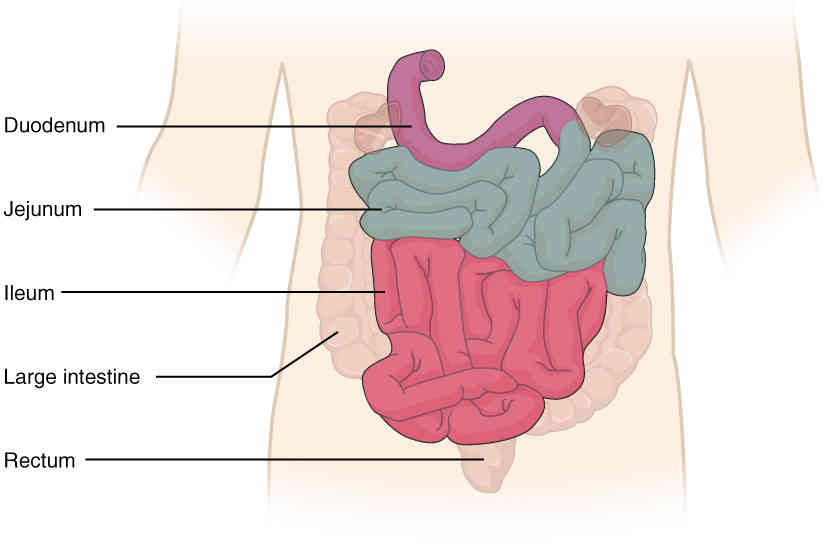

This page is under construction. For now, it is just a resource of the images found in the OpenStax Anatomy and Physiology Handbook. It wil slowly change into a revision tool. Each slide has a number. Use this to refer to the slide. When completed, it will have an unlabelled section, with labelled slides in parallel. On the unlabelled slides, write your answer and use the labelled slide to assess yourself. Keep track by also noting the number on each slide. Improvement at each attempt is important, more so than full marks on a first attempt.